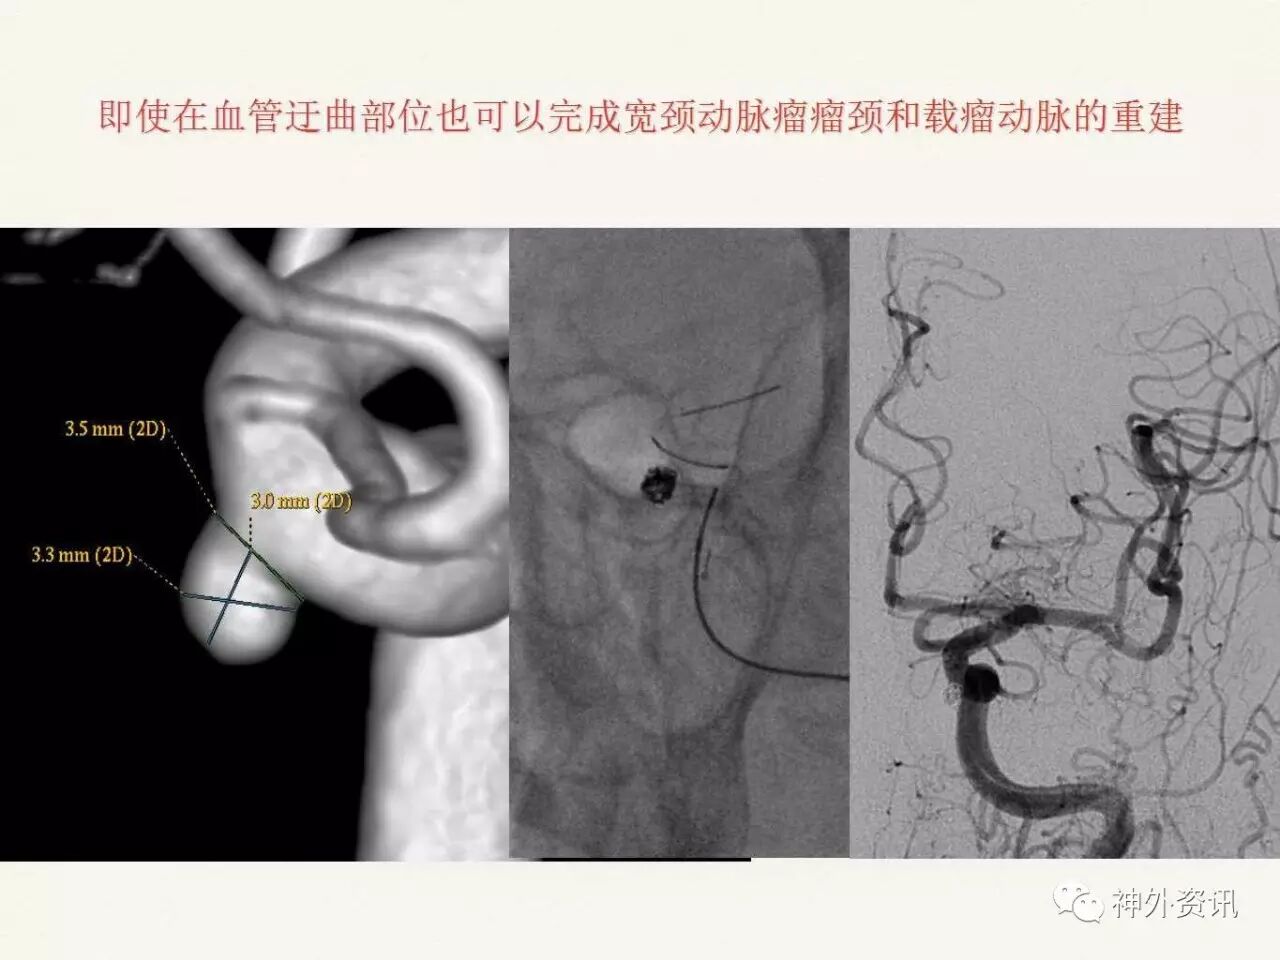

在东北地区率先开展了颈内动脉、大脑中动脉及基底动脉闭塞血管内再通、颅内动脉栓塞急性期取栓、血流导向装置治疗大型宽颈动脉瘤等,对颅内动脉瘤、动静脉畸形、颈动脉及颅内动脉狭窄、颈内动脉海绵窦瘘、硬脑膜动静脉瘘等外科治疗具有较深的造诣。完成脑血管造影8600余例,各类脑血管病介入手术共4500余例,动脉瘤、动静脉畸形、脑肿瘤、脑出血及脑外伤等外科手术1500余例。